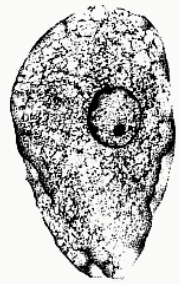

Dientamoeba fragilis troph